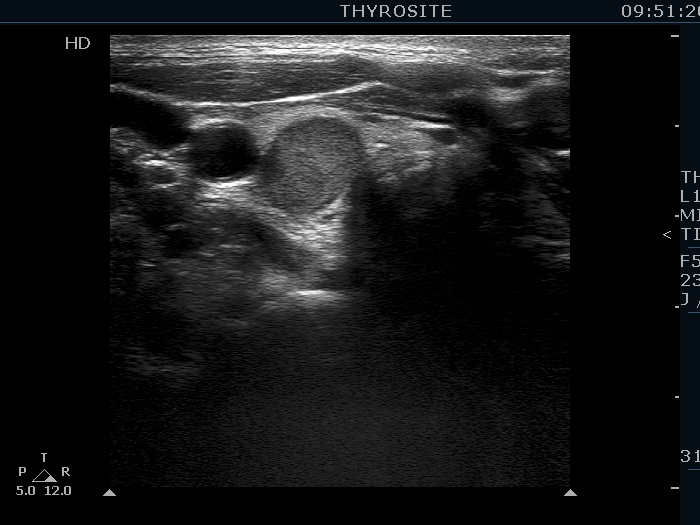

Clinical data: A 43-year-old woman was diagnosed with primary hyperparathyroidism. Scintigraphy disclosed an enlarged right lower parathyroid. The initial cause of evaluation was elevated serum calcium level detected by chance. The patient was referred in order to confirm and to accurately localize the lesion before surgery.

Ultrasonography. The thyroid was echonormal. There was a hypoechoic mass within the lower pole of the right lobe. The lesion was surrounded by thyroid tissue throughout.